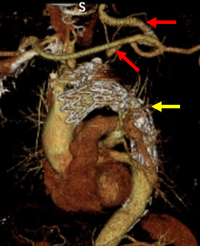

胸部大動脈瘤に対するハイブリッド手術

血管内治療(赤): 動脈瘤のある血管にステントグラフトを設置。動脈瘤への血流を遮断

外科手術(青): 閉塞した血管へバイパス(迂回路)をつくる。

デブランチ胸部ステントグラフト術

赤印:バイパス

黄印:ステントグラフト